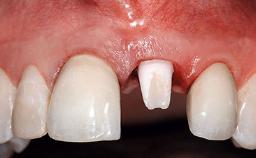

A 36-year-old male patient with a compromised maxillary central incisor was referred by his general dentist for consultation. The patient’s chief complaints were the gradual debonding of a temporary crown on the right central incisor and unsatisfactory esthetics due to an increasing diastema between the right central and lateral incisors. The patient reported a traumatic event some years previously, when a crown had been placed after root-canal treatment. The referring dentist wanted to provide a new crown restoration, but was concerned about the condition of the residual root. Anamnesis was negative for any other dental or periodontal pathology in the remaining dentition. The patient reported taking no medications: He was a smoker (10 to 15 cigs/day) and had realistic esthetic expectations.

Mesio-Distal Space Symmetry +/- 1 mm of contra-lateral tooth